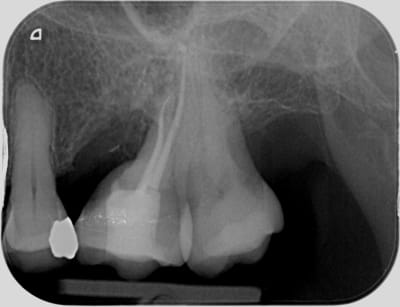

Evidemment le titre du sujet est racoleur, et ne va pas passionner les foules. Mais je trouvais intéressant de vous confronter à une technique que l'on a un peu oublié avec l'avènement des implants.

Pourtant, après un recul, certes pas très conséquent de 12 ans d'implantologie, j'avoue adopter à présent une attitude plus conservatrice, et me pose plus souvent la question de l'option de l'amputation radiculaire.

C'est pourquoi dans ce cas avec une furcation de classe 3 j'ai choisi la conservation de la 26 en me laissant donc la possibilité d'implanter dans quelques années si besoin.

Pour ceux d'entre nous qui ont été formés en paro avant la généralisation de l'implantologie, le TT conservateur de choix des lésions inter-radiculaires de cl 3 au maxillaire était l'amputation radiculaire à la condition expresse que l'anatomie du tronc radiculaire cervical se prête à une élimination complète de la plaque. Evidemment, sous lambeau muco-périosté avec une plastie cervicale visant à éliminer tout ressaut ou bombé résiduel. Si ces conditions sont remplies, les pronostics étaient plutôt bons. En général on préfère virer la rac DV que la MV... ensuite tout dépend de l'endo bien sur... faut être sur qu'il n'y a pas un MV2 oublié qui va fiche le bazar à court terme... car bien sur si ça évolue en lésion endo paro, sur le plan osseux c'est le désastre.